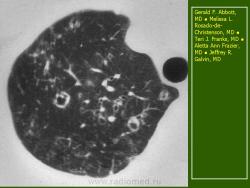

В 5 наблюдениях (21%) из больных с распространенной формой заболевания отмечались изменения в легких в виде обогащения, избыточности легочного рисунка, его деформации по сетчато-петлистому типу, очаговых теней. Корневая и медиастинальная аденопатия отсутствовали. В 1 случае в легких выявлена киста, которая периодически осложнялась нагноением (Рис. 4).

Поражение легочной ткани (рис. 22) свойственно любому возрасту. Часто больные имеют общие симптомы — лихорадку, слабость, реже — кашель, одышку, боли в грудной клетке. На рентгенограммах отмечается деформация и усиление легочного рисунка и микроузловые инфильтративные тени. Поражение костного мозга (с наличием клеток Лангерганса) сопровождается цитопенией периферической крови.

Рис. 22. Поражение легких при Лангер-гансово-клеточном гистиоцитозе.